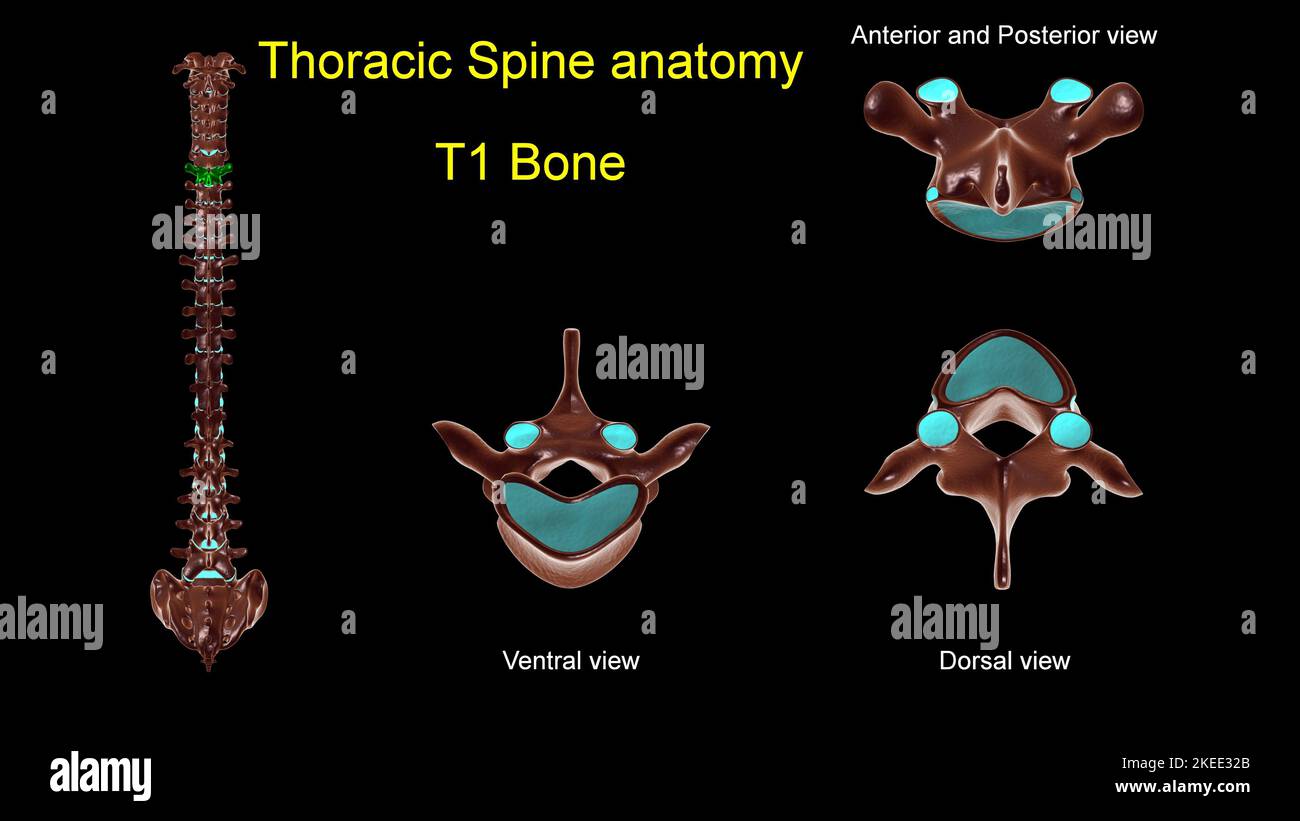

RF2KEE32B–Colonna toracica T 1 anatomia ossea per concetto medico 3D Illustrazione con vista anteriore e posteriore